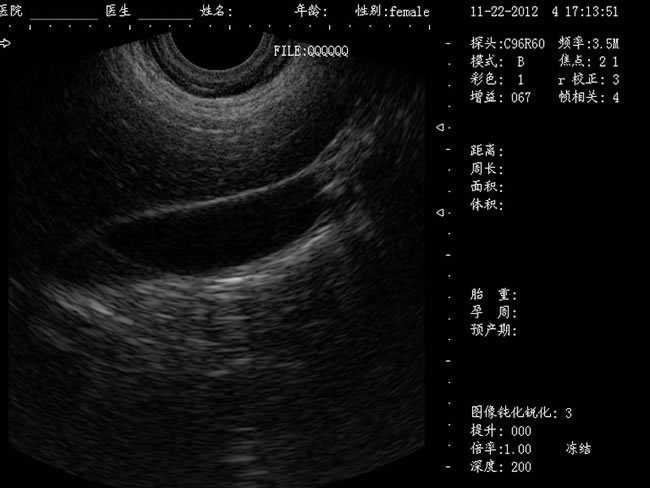

DW-460全數字超聲婦產科手術監視儀

DW-460

婦產科手術監視儀-可視人流機掃描角度:

a) 6.5MHz腔內探頭:152º可視可調;

b) 3.5MHz凸陣探頭:60º可視可調;